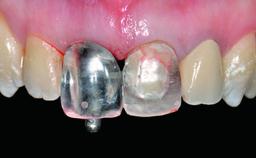

A healthy 37-year-old female patient was referred for a consultation on the replacement of missing tooth 21 with an implant-supported restoration. She stated that several years previously the tooth had been traumatically avulsed following a motor vehicle accident. The tooth was replaced with a three-unit fixed partial denture (FPD) immediately afterwards. Over time, she became disillusioned with the FPD and looked for a different option, including orthodontic therapy. She presented still in her orthodontic appliances, with the pontic sectioned free from the FPD but attached to the archwire. Her orthodontist felt that orthodontic treatment had been successfully completed, but nevertheless referred her before removing the appliances in case adjustments were necessary.

Retention Cemented, with prosthesis margin < 3mm submucosal Cemented, with prosthesis margin < 3mm submucosal

Provisional Implant-Supported Prosthesis Prosthodontic margin > 3 mm apical to mucosal margin Prosthodontic margin > 3 mm apical to mucosal margin